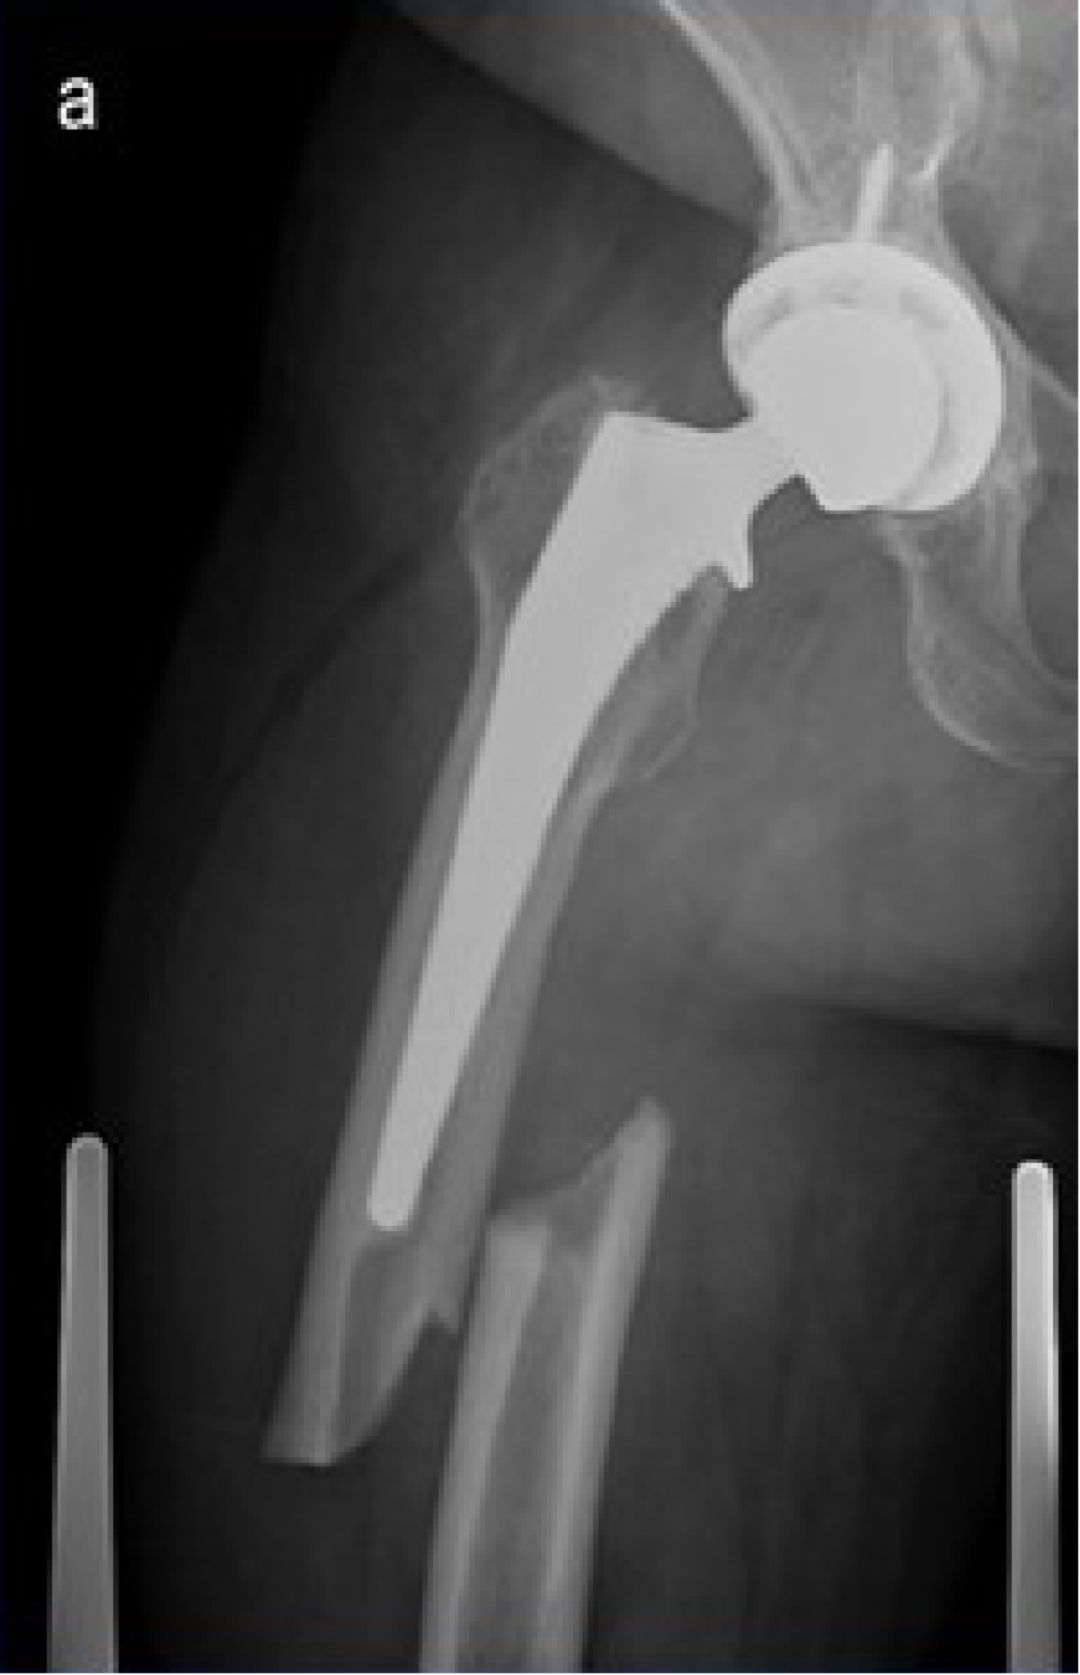

6. 假体周围骨折:

发病率 1%~2%。可发生在书中或术后。迟发性骨折多发生于股骨假体尖端。非骨水泥假体植入和翻修术更容易发生术中骨折。

B1 型假体柄固定牢固